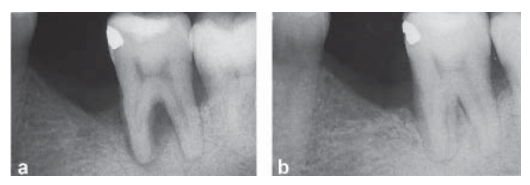

Figura 1

Aspecto radiográfico de um defeito na área de furca antes do tratamento (a) e 6 meses após o tratamento (b).

Paciente apresenta-se com mobilidade dentária grau 2 no elemento 37. Uma área radiolúcida pode ser vista na radiografia (Fig. 1-a). À sondagem, não foi detectada bolsa periodontal na região de furca, apenas 6 mm no sítio distal e 5 mm no sítio mesial.